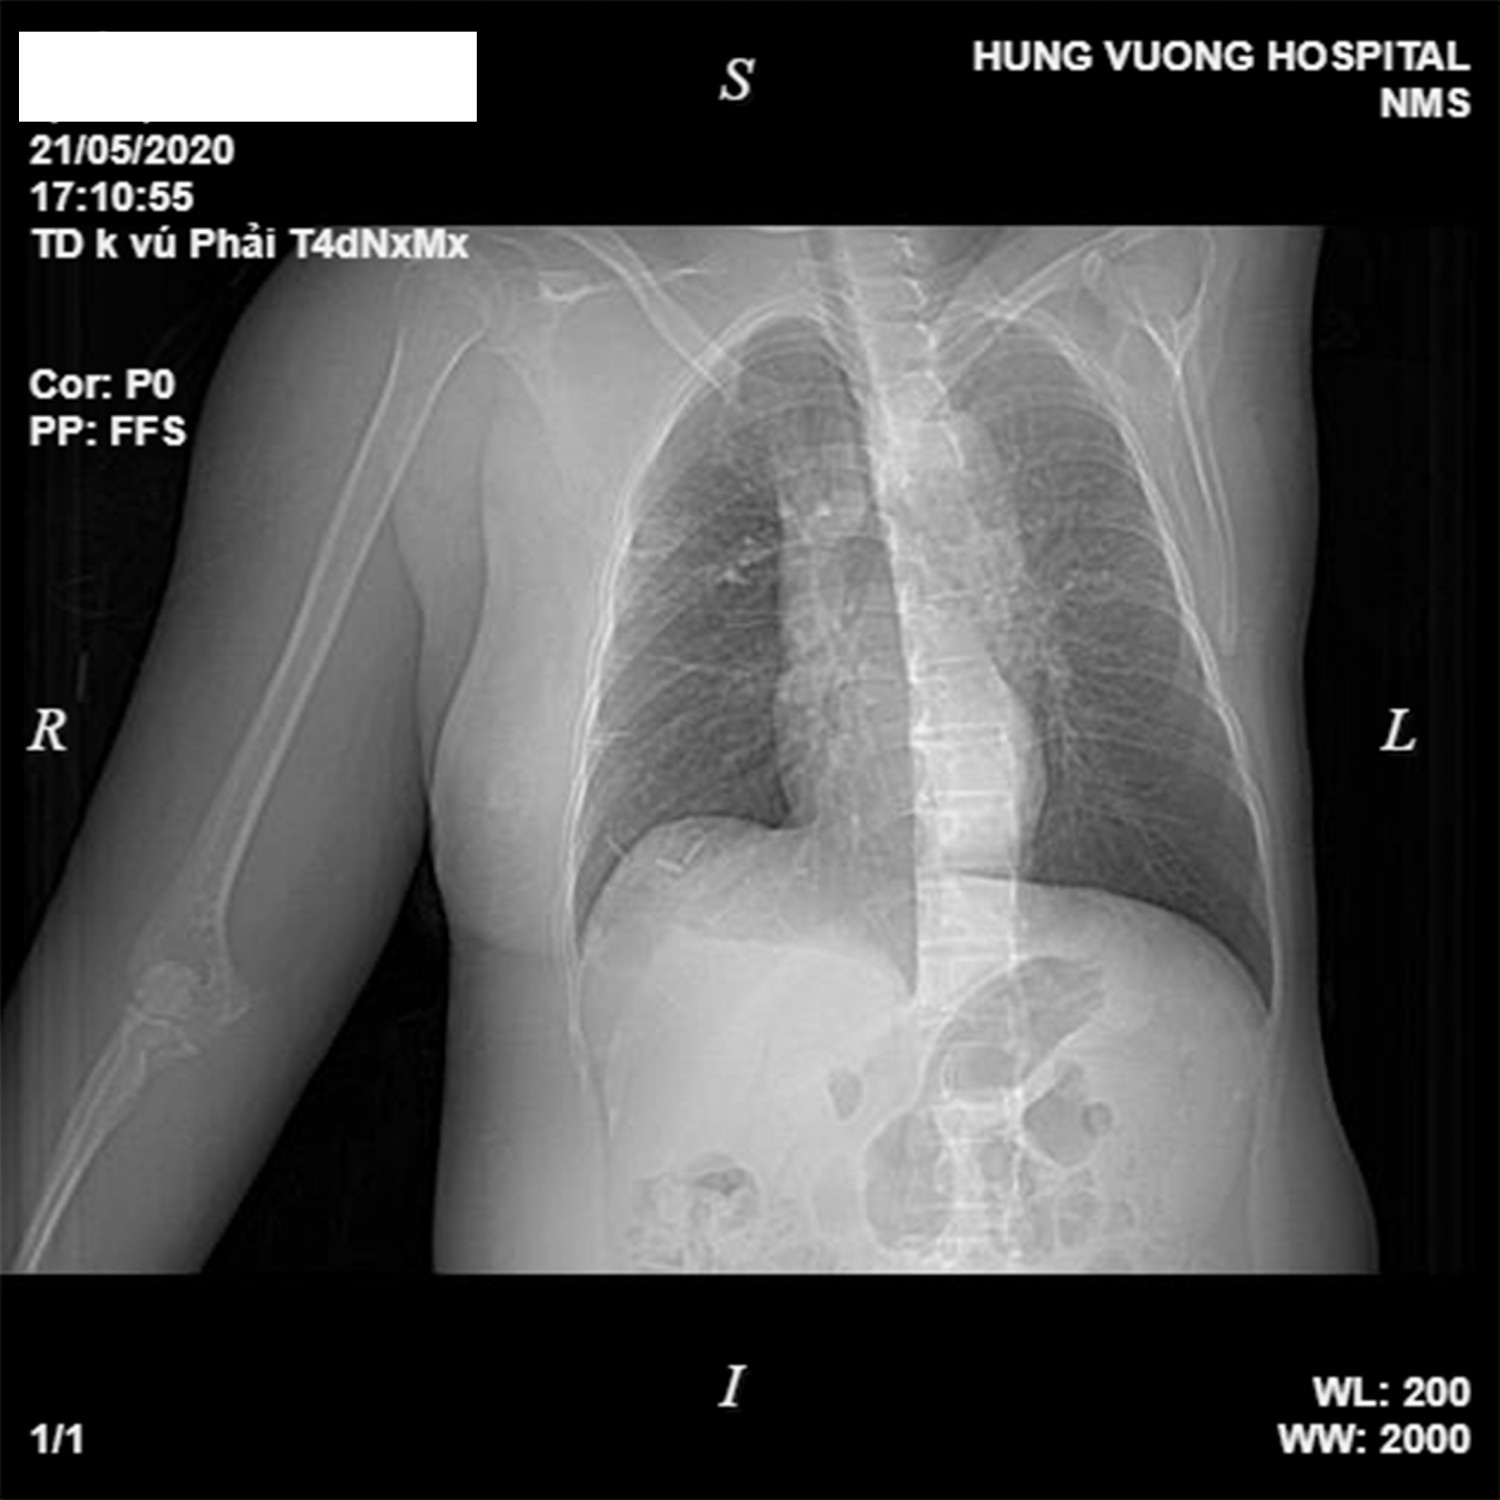

Bác sĩ chẩn đoán bệnh nhân bị ung thư vú giai đoạn cuối, di căn hạch nách và xương cánh tay phải. Ảnh: BVCC.

Sau khi kiểm tra, các bác sĩ chẩn đoán bệnh nhân bị ung thư vú giai đoạn cuối, di căn hạch nách và xương cánh tay phải. Vùng đắp thuốc nam bị nhiễm trùng, có nguy cơ hoại tử, nhiễm khuẩn huyết nếu không được điều trị kịp thời.